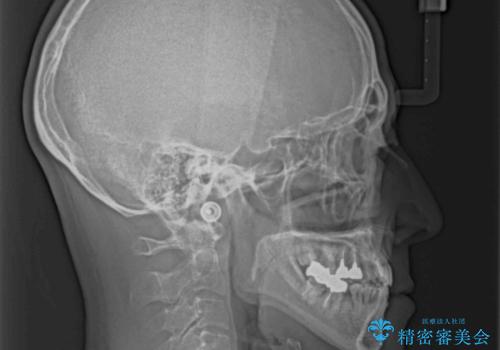

- 前歯のクロスバイトを気にして来院された患者様です。

骨格的に下顎が前方位ではありますが、歯並びが改善されれば正常咬合となることが分かったため、インビザラインを用いて咬み合わせを改善していくこととしました。